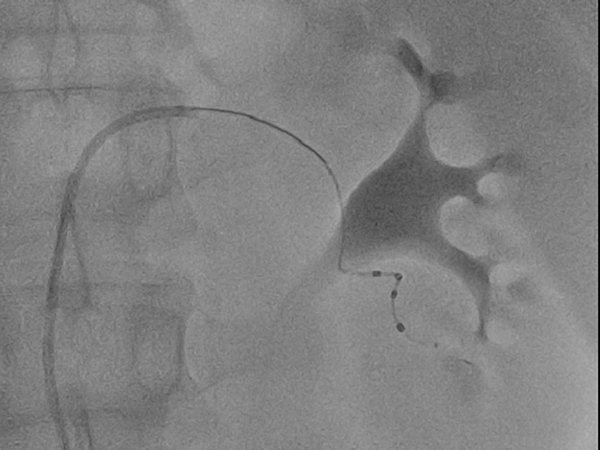

手术采用局麻+镇痛模式,用时1个半小时,穿刺右股动脉后,消融导管分别进入左右肾动脉,消融双肾动脉主干及分支共62个靶点,对肾动脉进行了全面、完整地消融,无肾动脉狭窄、夹层等并发症,手术获得圆满成功。